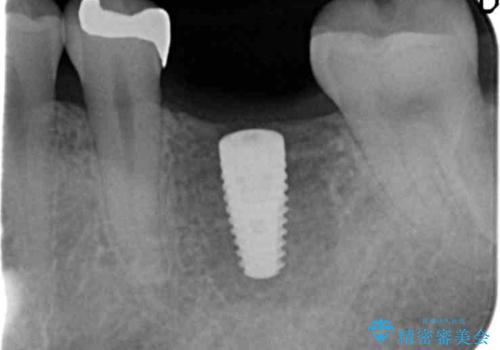

抜歯後、骨の再生を待ったことで、清掃性の高い位置に埋入を行い機能的・審美的なインプラント治療を行うことができました。